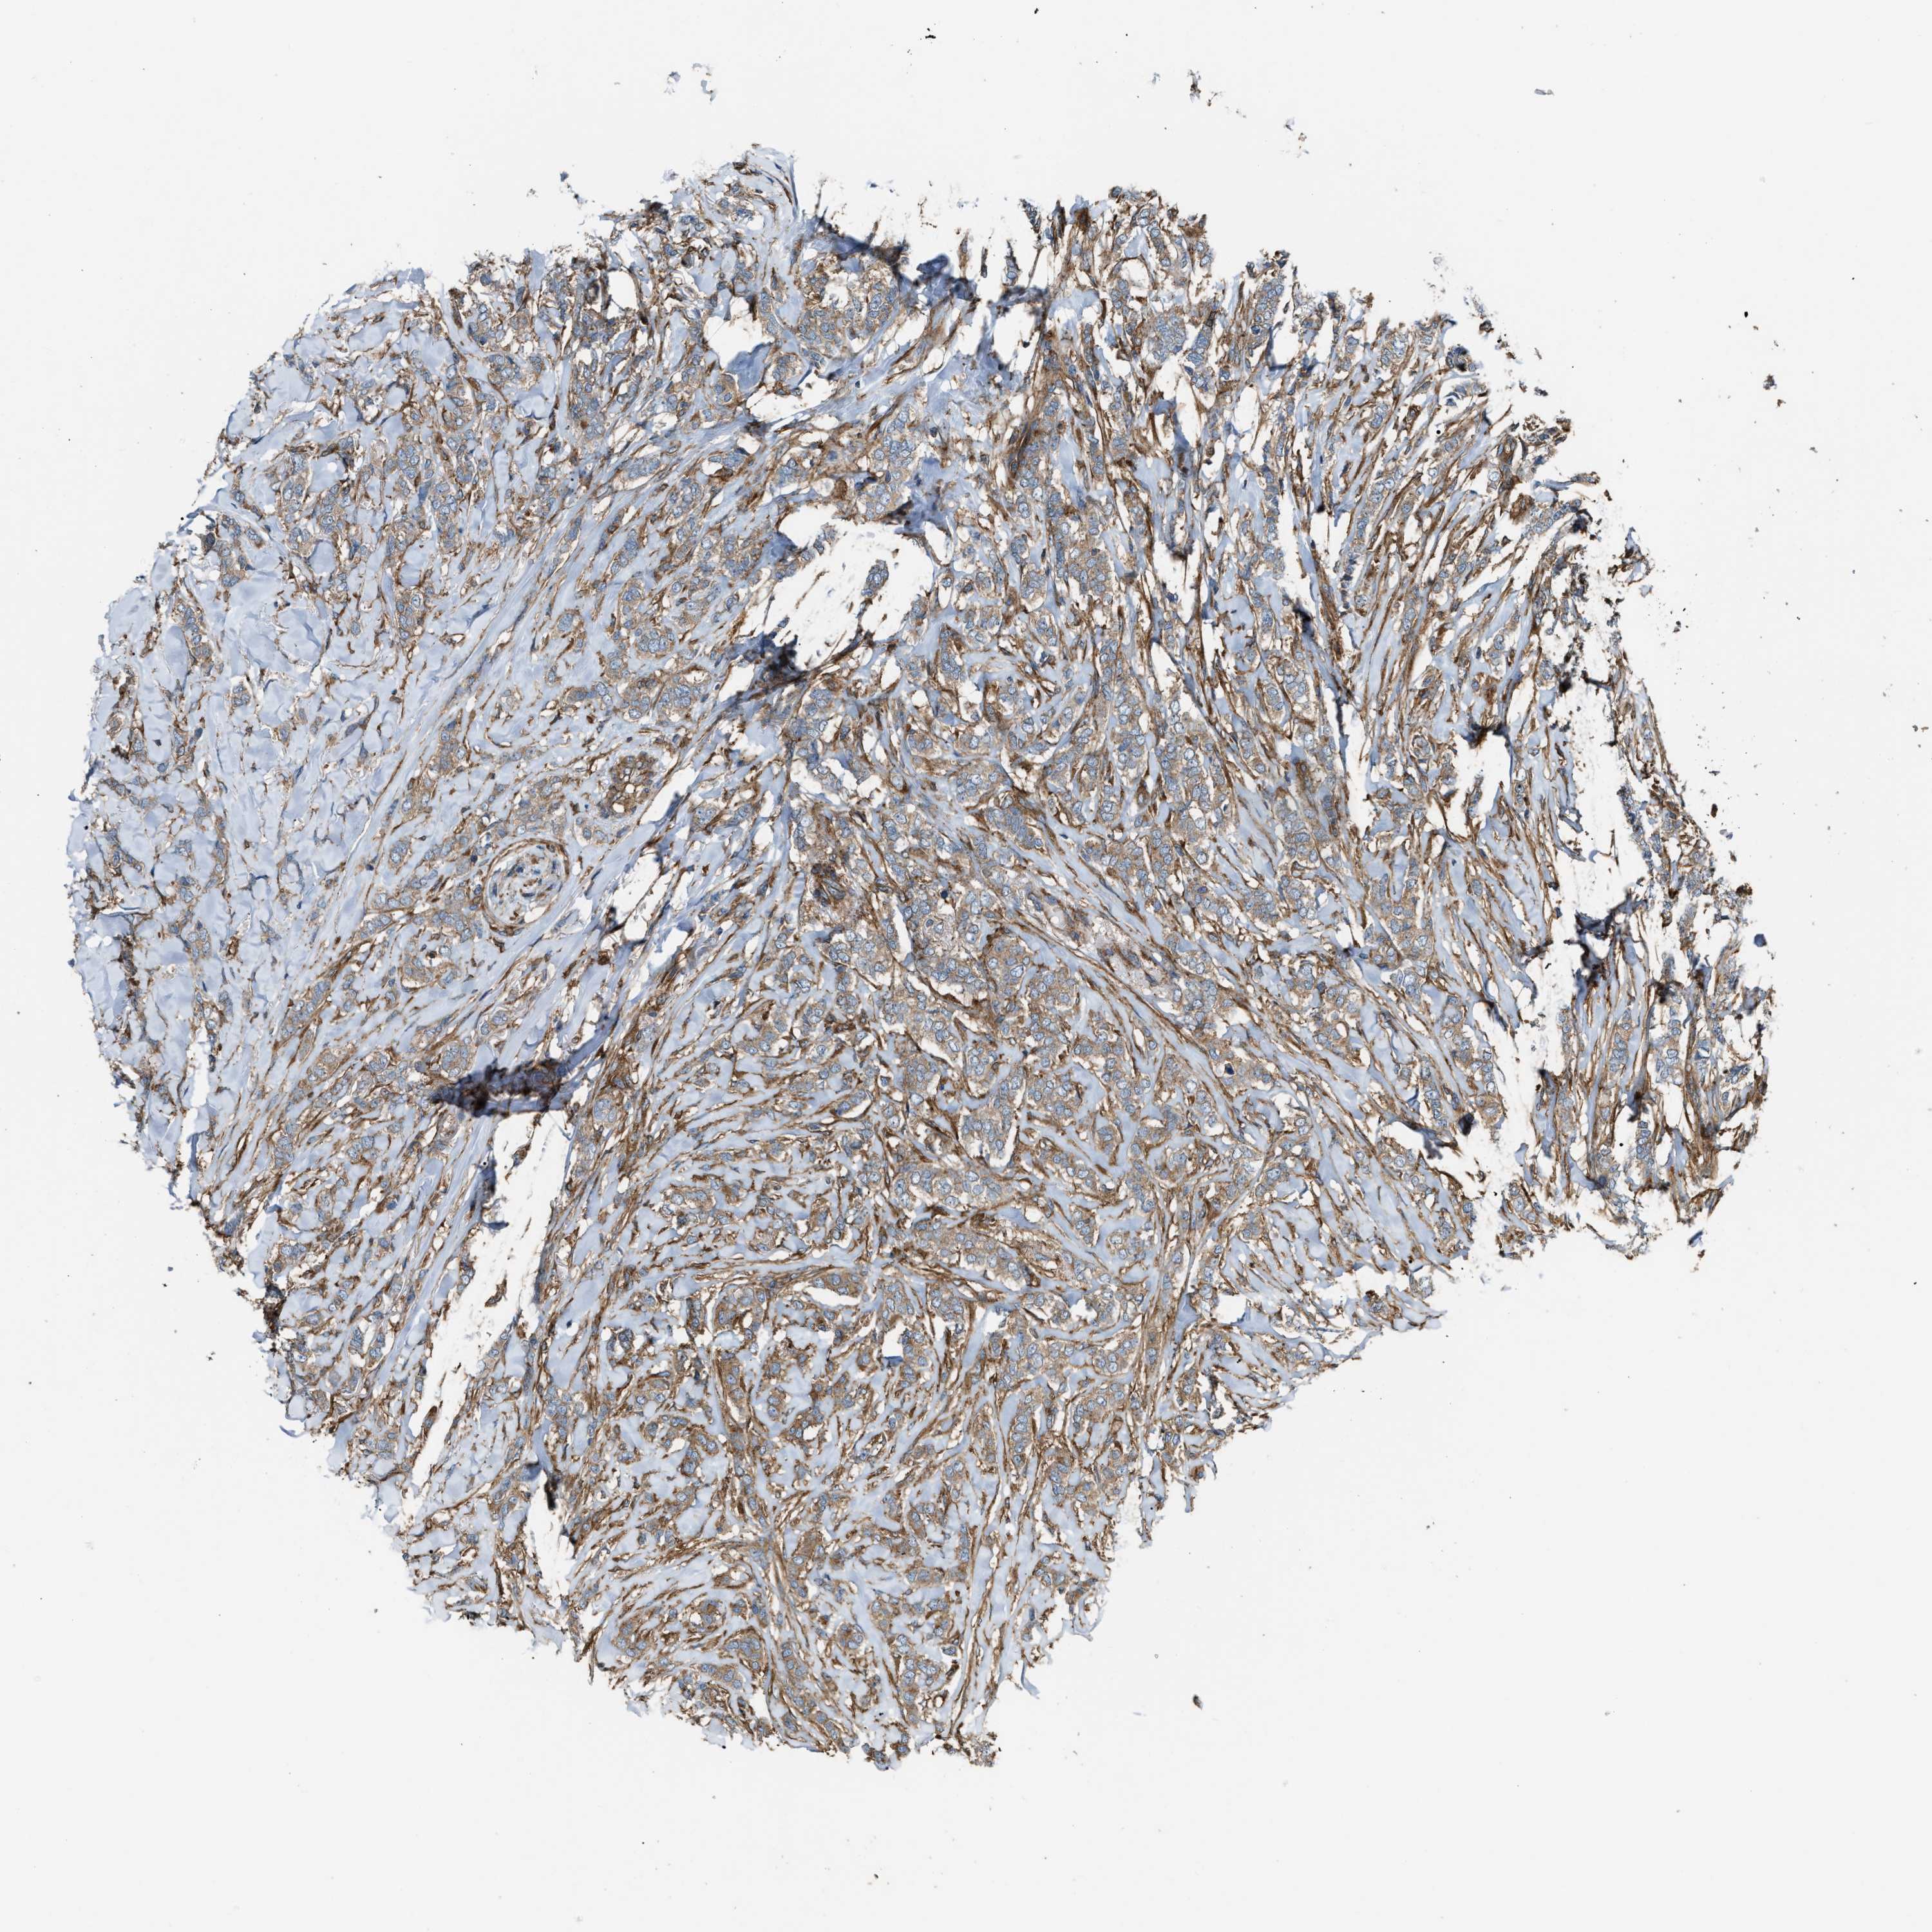

CANCER BREAST CANCER Show tissue menu

BRCA TCGA BRCA VALIDATION PROTEIN EXPRESSION